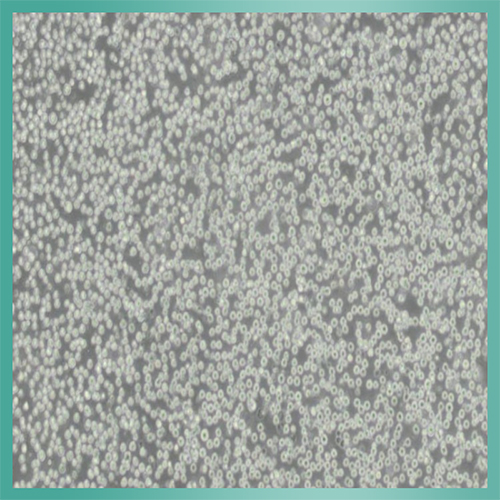

YAC_小鼠淋巴瘤细胞背景描述:YAC-1是一个淋巴瘤细胞,将Moloney白血病病毒(MLV)接种到新生A/Sn小鼠中生成。YAC-1细胞对NK细胞的活动敏感,对于NK细胞活性检测十分有用。

生长特性:悬浮细胞

细胞形态:淋巴母细胞样